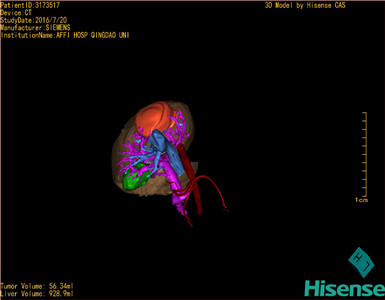

肝细胞肝癌-CH-001-LT-000341

将0.625mm双源薄层CT资料的静脉期和动脉期Dicom格式文件导入海信CAS系统。

通过调节窗宽窗位调整CT序号,对肿瘤,肝实质,胆囊,下腔静脉,肿瘤,肝动脉、门静脉及肝静脉等进行三维重建;系统自动计算肿瘤体积和肝脏体积。

模拟手术操作,自动计算切除肿瘤体积。肝脏体积为928.9ml,肿瘤体积为56.34ml,肿瘤体积为肝脏体积的6%,通过比对60-70岁正常肝脏体积为1262.7±284.31 ml,通过术前模拟手术,精准判断切除后剩余肝脏体积能耐受,避免肝衰竭发生。

术前手术方案的规划。

手术顺利,麻醉满意,解剖标本,肿块直径约5cm,灰白色,家属过目后送病理检查。病理检查结果:(右叶)肝细胞肝癌,II-III级。手术时手术者可开启Hisense CAS系统手势控制功能,对肿瘤的解剖结构进行实时、全方观察、评估,起到术中导航作用。

术前三维重建:

重建图片